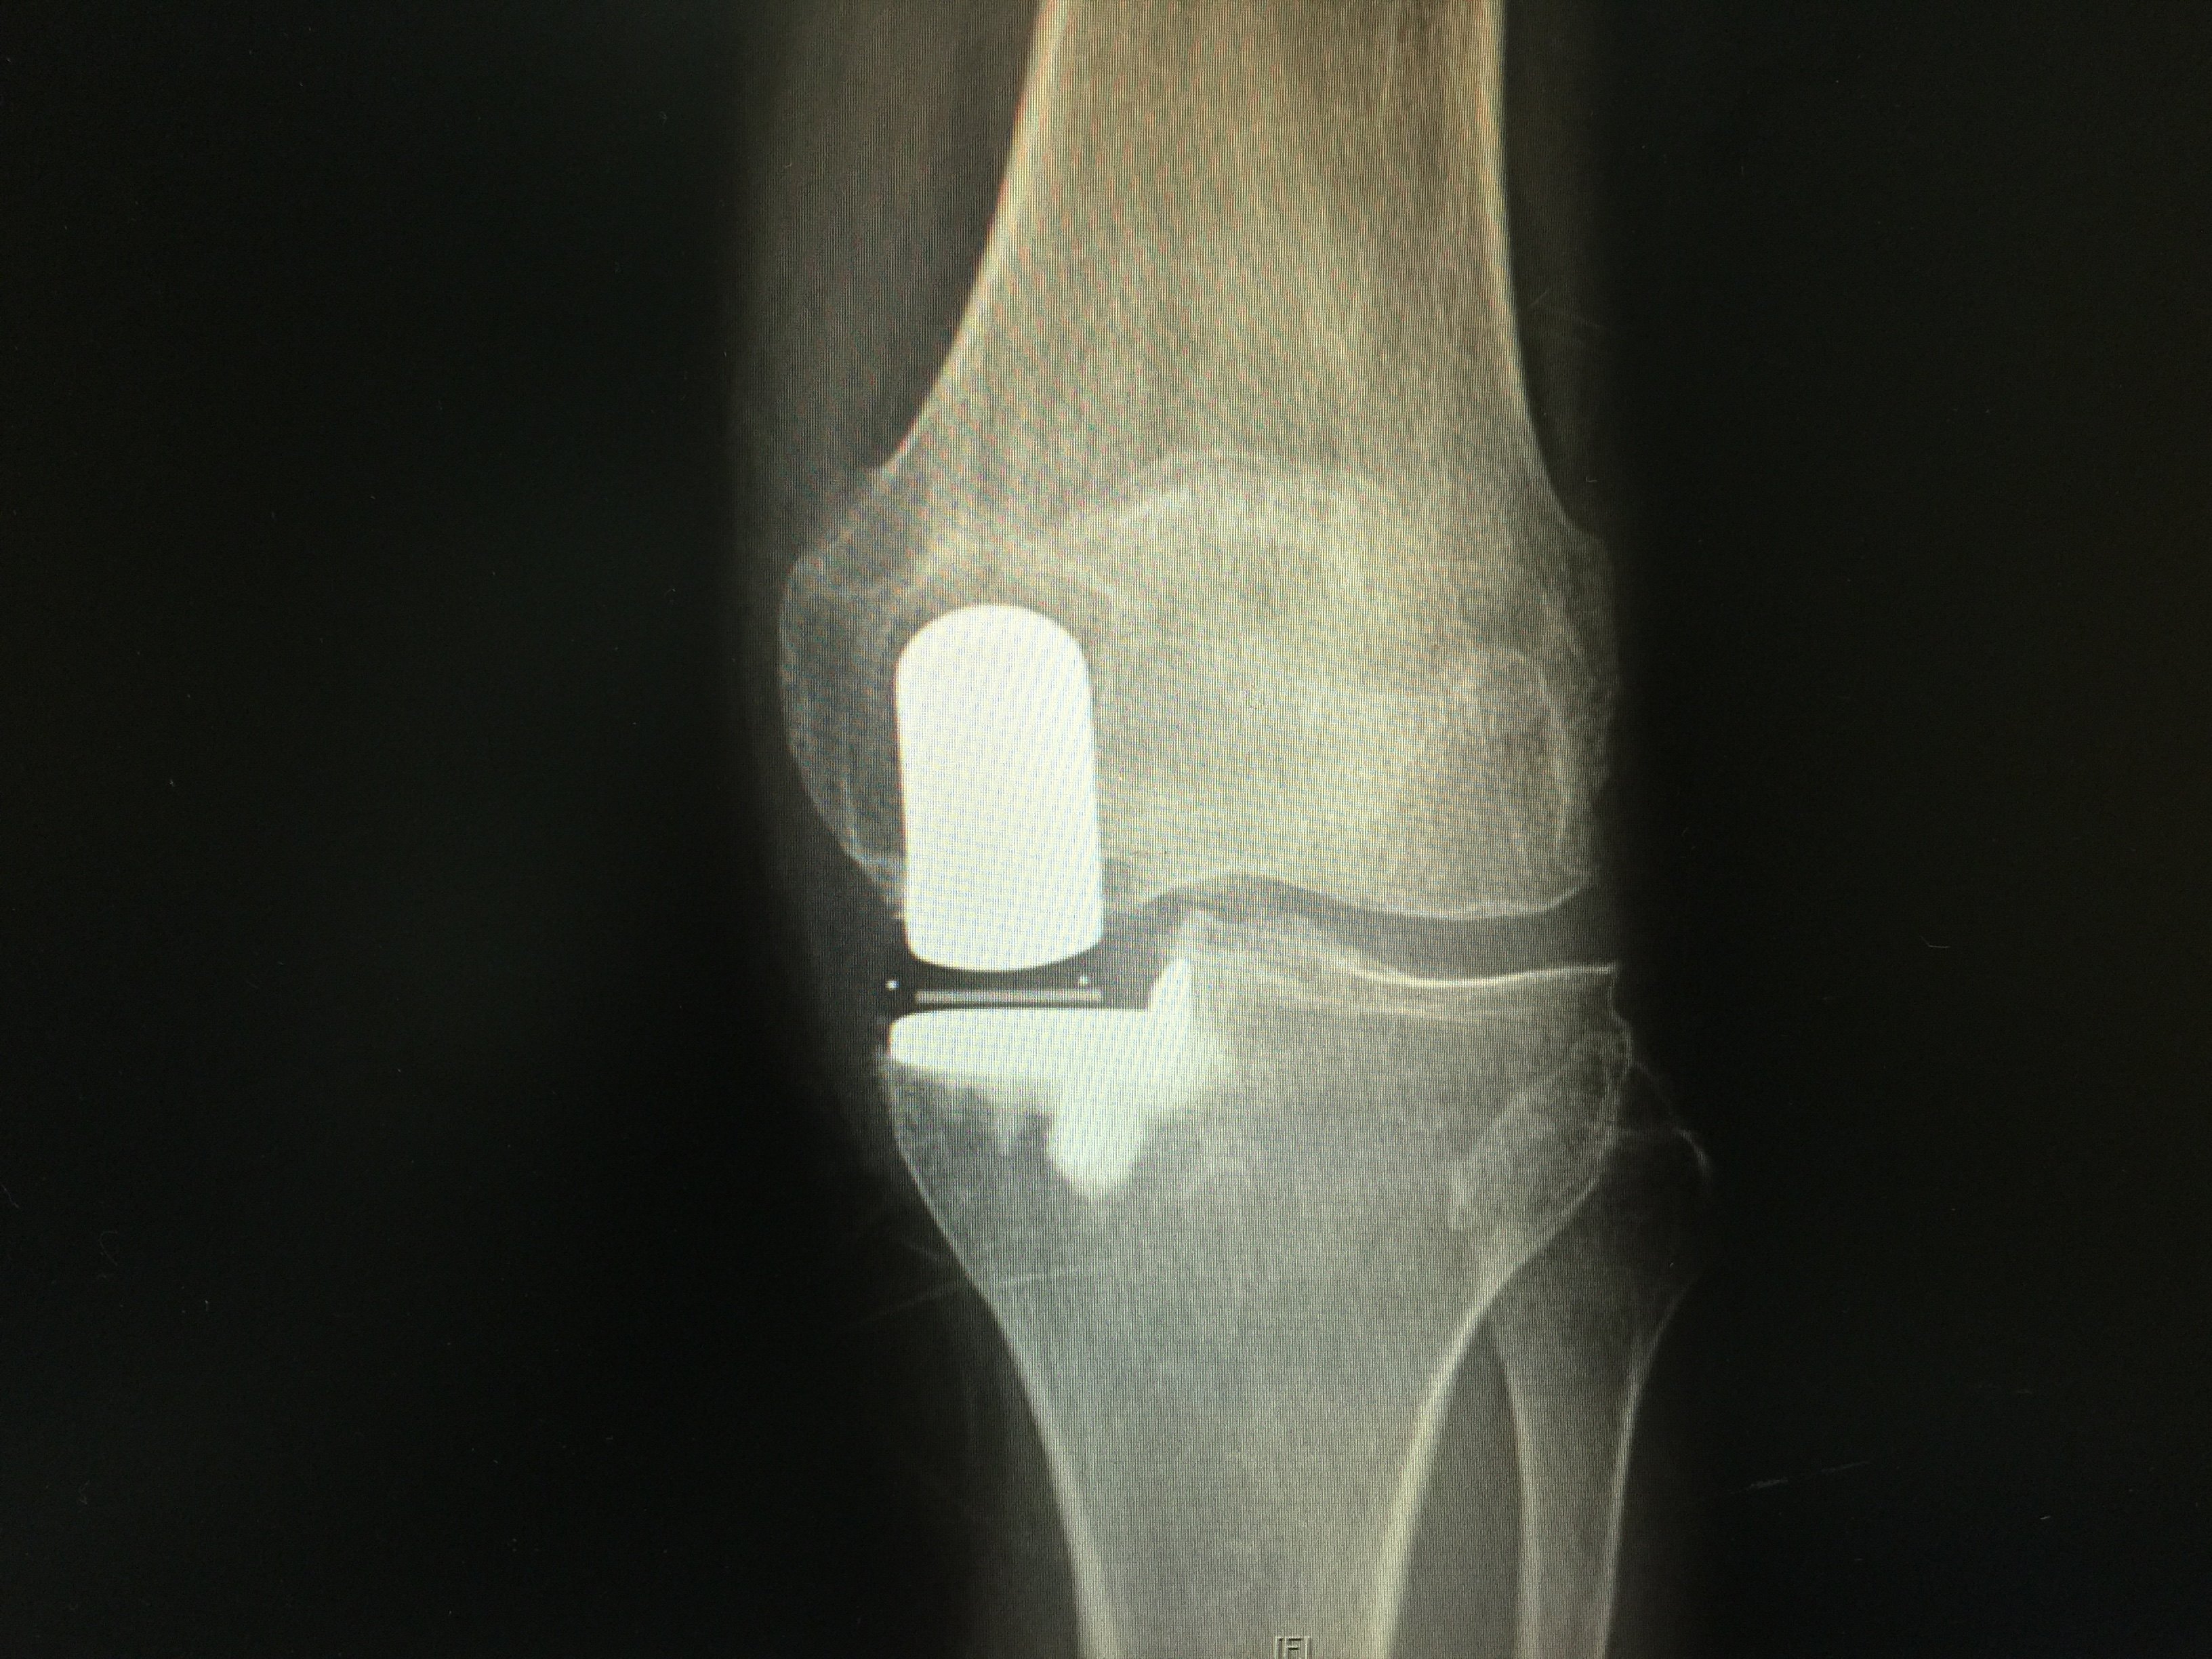

60岁女性,膝关节骨性关节炎.微创单髁置换术. - 好大夫在线

图片尺寸960x1280